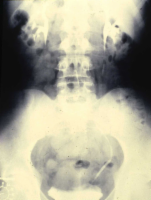

Das Ausscheidungsurogramm ergab eine stumme Niere links (Abbildung 18c). Die retrograde Sondierung zeigte eine deutlische Kompression des Harnleiters sowie eine verkleinerte Niere links mit destruierten Kelchen (Verplumpung) (Abbildung 18d).

Die Röntgenübersicht der Niere und ableitenden Harnwege zeigten keinen Anhalt für Konkrement. Im Ausscheidungsurogramm eine "stumme Niere" links (Abbildung 19a). Bei der retrograden Sondierung links fand sich keine Abflussbehinderung (Stein oder Stenose) (Abbildung 19c). Im MCU kein Anhalt für Reflux (Abbildung 19b). Im Nierenfunktionsszintigramm MAG3 wurde eine seitengetrennte Funktionsverteilung von rechts zu links wie 93% zu 7% festgestellt. Zur Abklärung eventueller Gefäßalterationen erfolgte eine Renovasographie mit dem Nachweis einer langstreckigen Stenose der linken Arteria renalis (Abbildung 19d). Wegen des Verdachtes auf eine generalisierte Arteriitis wurden Angiographien weiterer Gefäßgebiete durchgeführt: Dabei fanden sich eine geringgradige Einengung der infrarenalen Aorta und der linken Arteria subclavia.